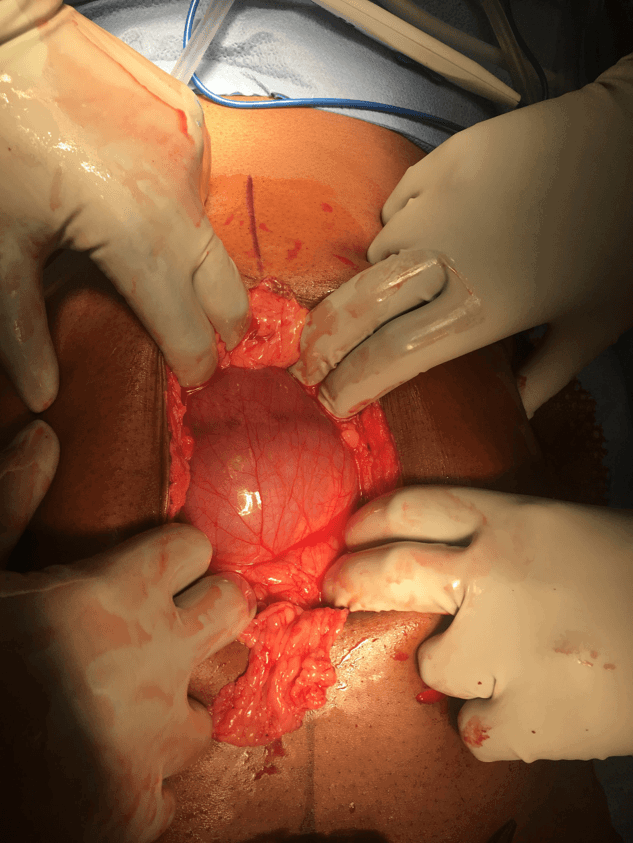

In the operating room, the case was attempted laparoscopically at first, but due to bowel dilation and torsion of the small bowel underneath the transverse mesocolon, the decision was made to convert to a laparotomy. Upon opening the abdomen, the majority of the small bowel was found to be herniated up into the lesser sac. After lysing adhesions and opening a large hernia sac, a congenital left paraduodenal hernia was identified. Bowel was reduced through the defect to its natural position inferior to the colon and the hernia sac was excised. The abdomen was then further explored with normal appearing anatomy otherwise. The paraduodenal hernia was closed using four interrupted silk sutures. The abdomen was copiously irrigated and the fascia and skin were closed primarily. Some representative images from the case can be seen below.